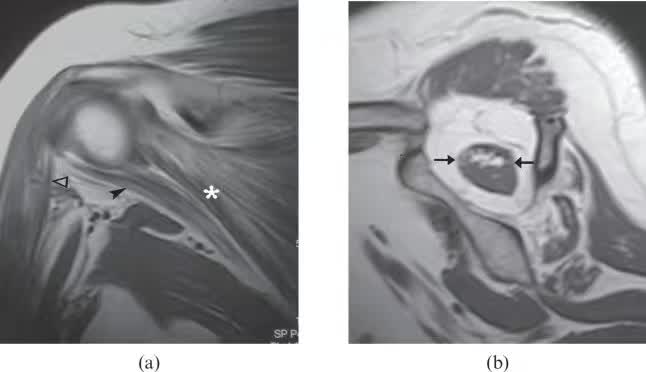

图14.一个58岁的女性慢性废用,经常发生肩部脱位,导致她的右臂使用有限。 (a)由于废用,冠状T1加权磁共振图像显示大量脂肪浸润的冈下肌(星号),小圆肌(箭头)和三角肌(开放箭头)肌肉。(b)矢状T1加权的MRI图像显示冈上肌萎缩和脂肪浸润(箭头)。